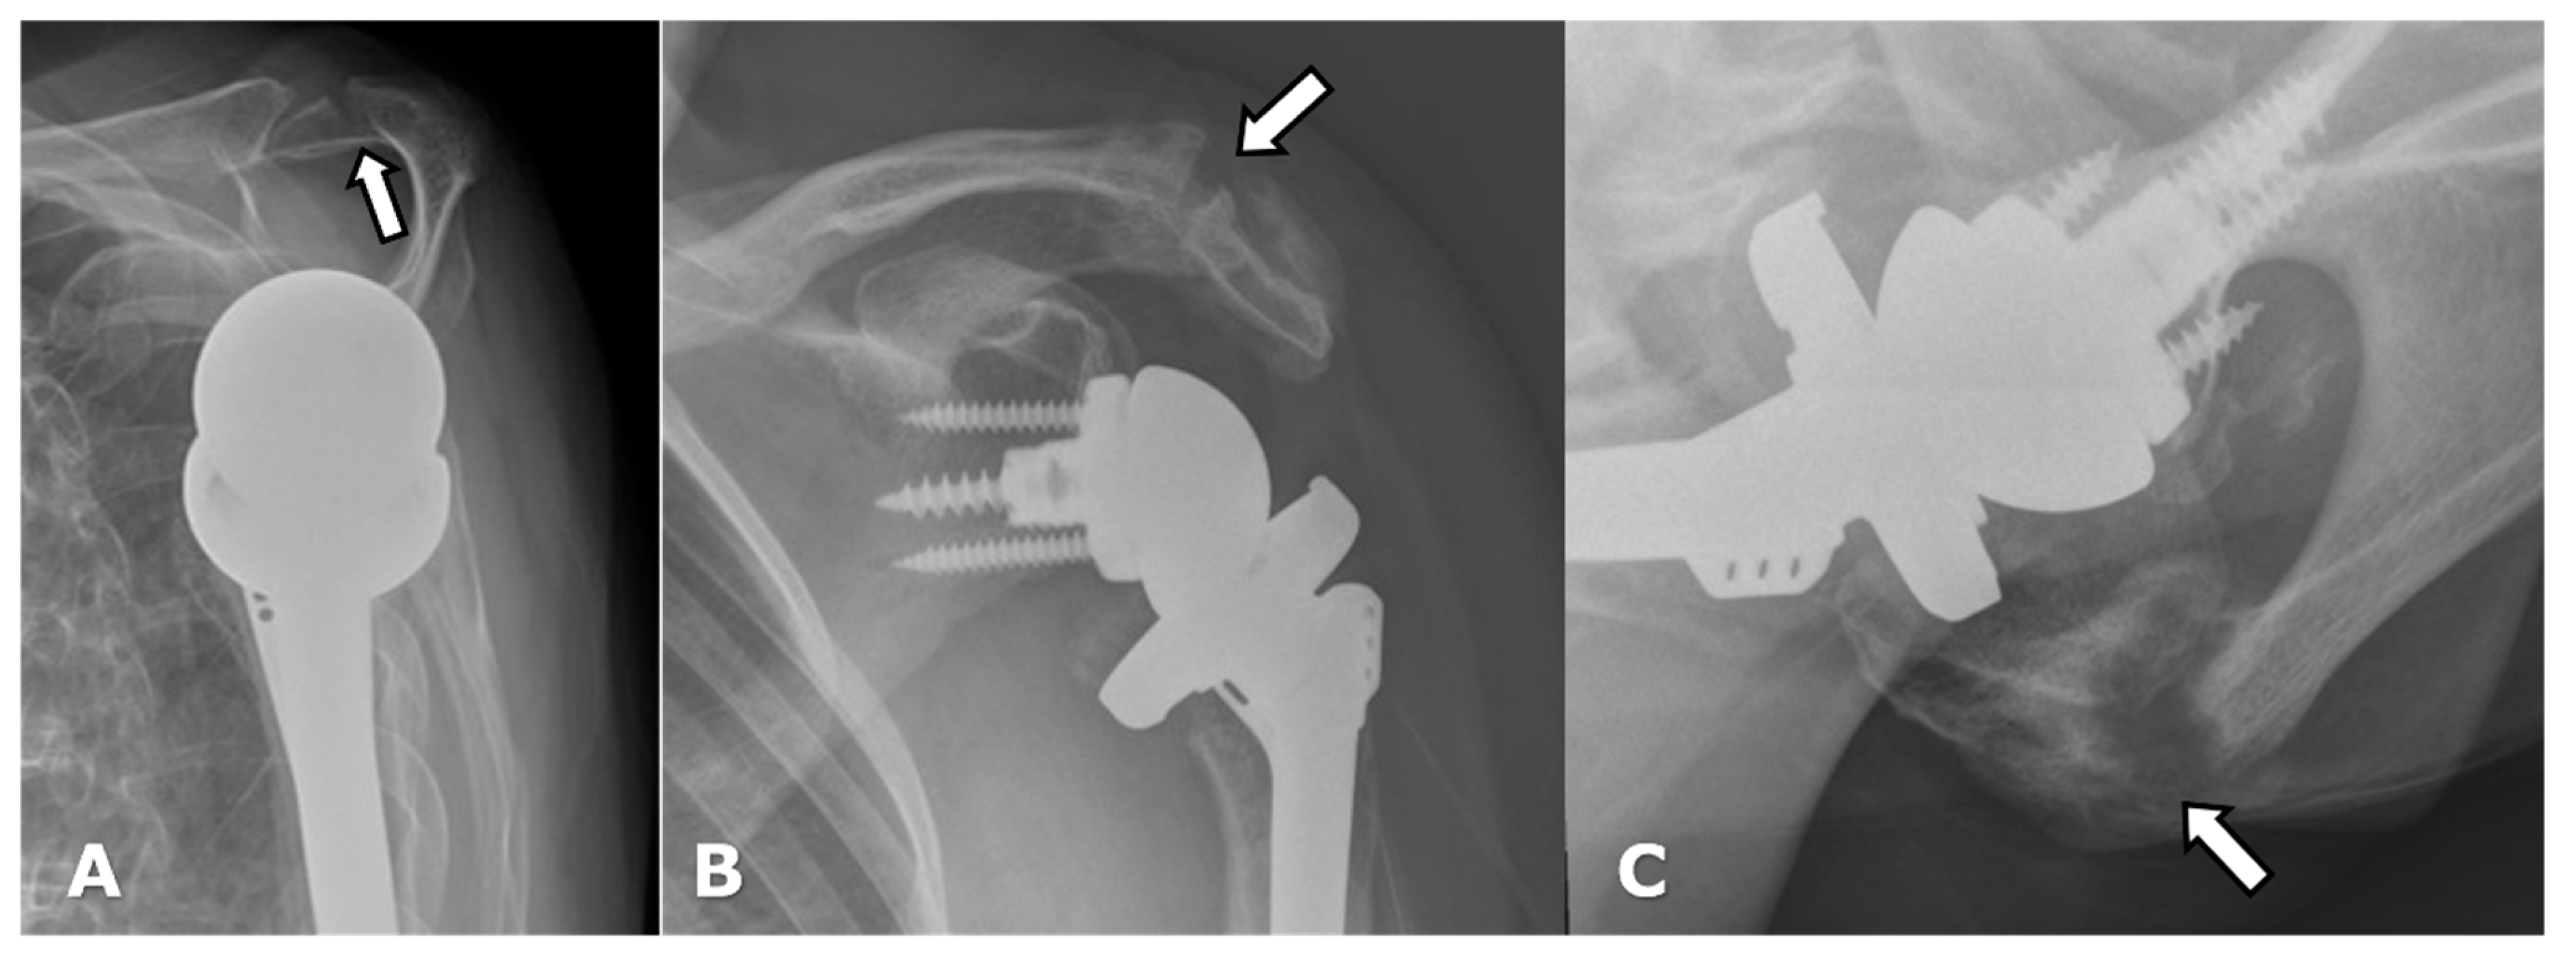

4.2.1. Loosening and Hardware Dissociation

4.3. Unique Complications

5.2. Reverse Arthroplasty

Reverse Total Shoulder Arthroplasty (RTSA)